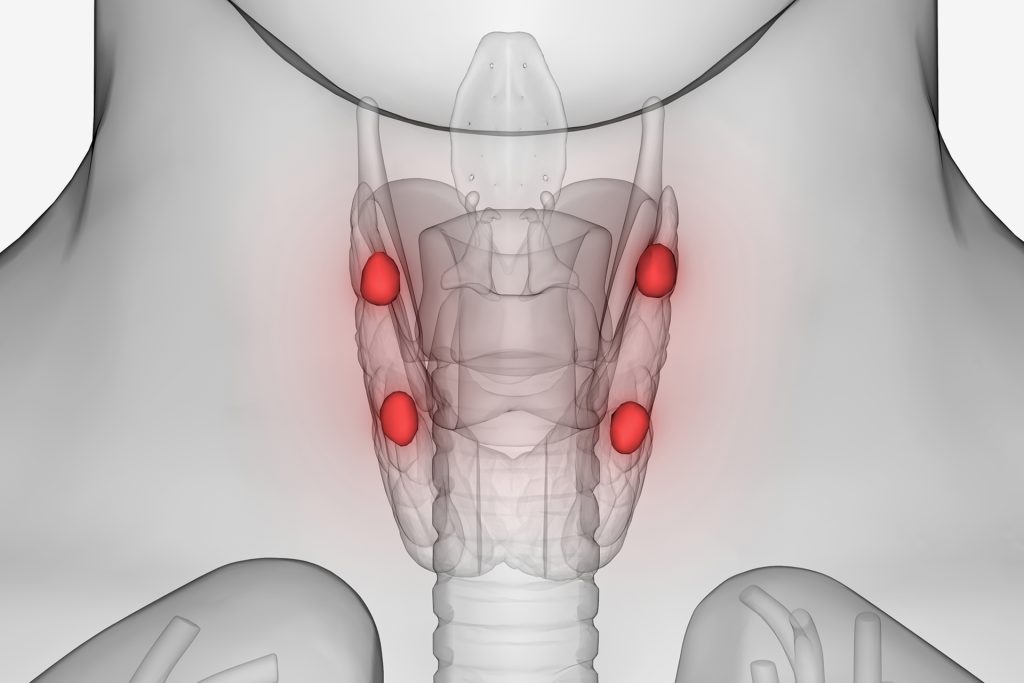

تقع الغدد جارات الدرقية خلف الغدة الدرقية في الرقبة، وتفرز الهرمون الدُّرَيْقي ((PTH) Parathyroid Hormone) الذي يلعب دورا محوريا في الحفاظ على مستويات الكالسيوم في الدم والعظام.

قال استشاري الغدد الصماء والسكري، الدكتور فوزات الشناق، إن الغدد الجارات الدرقية، أو ما يُعرف بالدريقات أو الغدد الجنب درقيّة، هي غدد صماء صغيرة جدا تقع في الجدار الخلفي للغدة الدرقية، وغالبا ما يكون عددها 4. وتقوم هذه الغدد بإفراز الهرمون الدُّرَيْقي، الذي يلعب دورا مهما في المحافظة على مستوى الكالسيوم في الدم من خلال تأثيره على العظام، الكلى، والأمعاء. وتمتاز هذه الغدد بحجم صغير جدا لا يتعدّى حجم حبّة الأرز، إذ يبلغ وزنها نحو 30 مليغراما لدى الرجال و35 مليغراما لدى النساء.